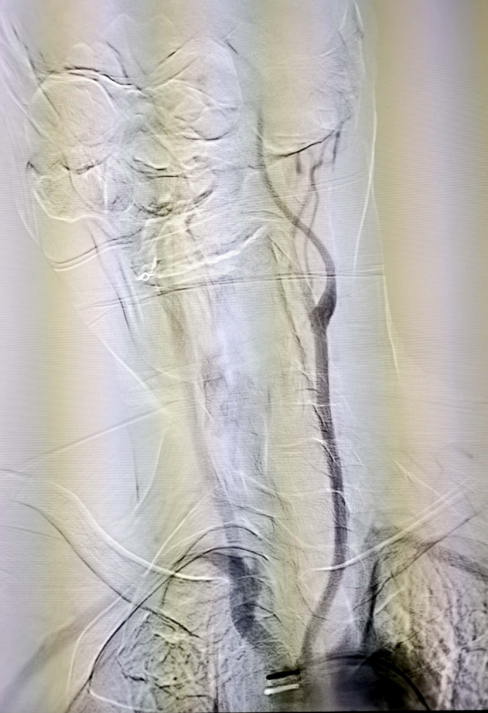

弓上脑血管造影

当天15点47分,一位老年男性患者在家中看电视时突发右侧肢体活动不灵,不能言语,家属紧急将其送往我院急诊就诊并联系神经内五科迟景宏主任。16点40分,患者在家属陪同下来到我院急诊。迟景宏主任在紧急查看患者病情并完善相关检查后,果断判断患者为急性大血管闭塞,通过与患者家属交代病情,征得了患者家属的同意,决定对其行静脉溶栓治疗。经验丰富的迟景宏主任判断单一溶栓难以缓解患者大血管闭塞所导致等症状,立即请介入放射科刘琳主任、莫庆国副主任进行会诊,建议桥接取栓。17点25分,患者顺利完成主动脉弓上脑血管造影证实左侧大脑中动脉下干闭塞。根据患者病情,神经、介入团队经商议后决定行BADDASS治疗,三件套组合:BGC+中间导管+长取栓支架,交换8F动脉鞘,引入BGC:8F×95cm;颅内支持导管:5F*125cm;取栓支架:4mm*20mm至远端病变血管,透视下释放取栓支架至病变血栓处,停留8分钟后取出大量血栓,一次取栓成功,达到三级再通。复查造影见左侧颈内动脉、左侧大脑前动脉、左侧大脑中动脉显影正常,血流改善,各分支显影良好,M1段未见明显狭窄,术中复查C臂CT未见颅内出血。19点10分,手术顺利结束,术后患者意识清楚,肢体活动较前明显改善,后经对症及康复治疗,患者于2月1日顺利出院,出院时患者恢复如常。通过医生的准确判断、过硬的医疗技术、团队的紧密配合,患者从入院到成功救治在150分钟内顺利完成。